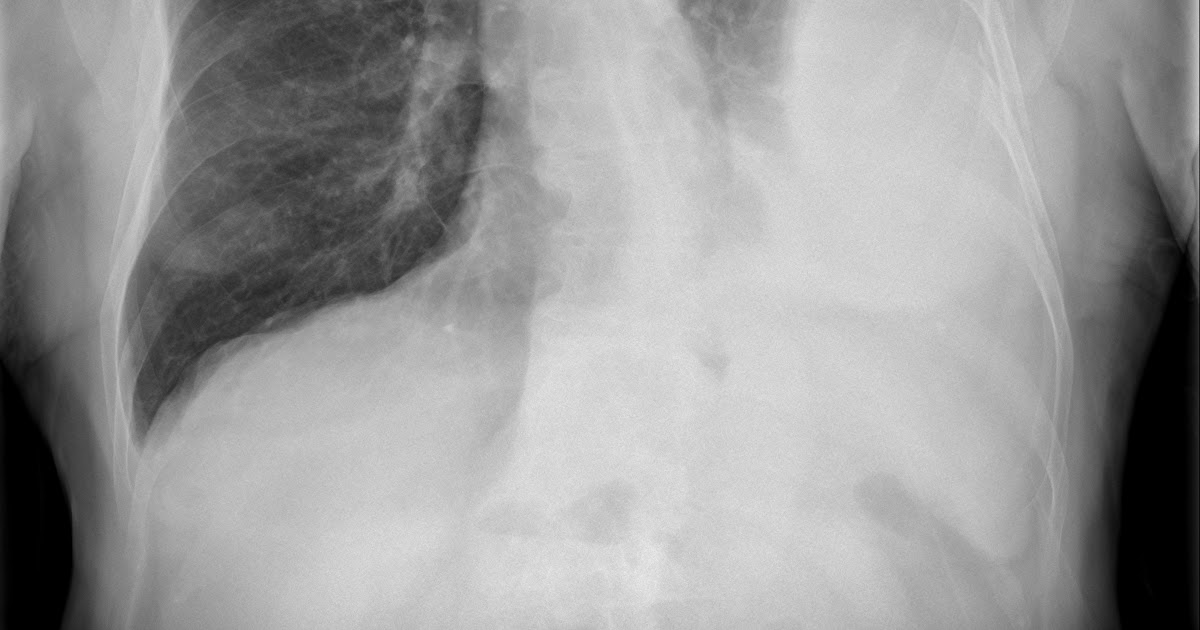

A contrast enhanced ct thorax scan showed a loculated pleural effusion encasing most of the right hemithorax with medial extension to the azygo fig. D, abdominal ct scans showing ascites (arrows). Characteristic ct findings include the split pleura sign (enhanced pleurae that surround a loculated effusion), pleural thickening, and. Ct scan of the chest of a patient with large loculated pleural effusion in his left thoracic cavity. Common causes of this condition include infection, malignancy, autoimmune disorders, or volume overload.

Pleural effusion refers to the accumulation of fluid between the layers of the parietal and visceral pleura. Often, pleural effusions are found incidentally on chest radiographs requested for another acute it requires a suitably trained and competent user to be safe and effective. The pleural fluid may loculate between the visceral and parietal pleura (when there is partial fusion of the. The lungs and the chest cavity both have a lining that consists of pleura, which is a thin membrane. Ct scan is the modality of choice for further assessment of pleural disease: Blood tests to check functioning of the kidneys and the liver. Pleural effusion volume was determined on each ct scan section; Loculated effusions on ct scans tend to have a lenticular shape with smooth margins, scalloped borders, and relatively homogeneous attenuation.

Pleura l effusion seen in an ultra sound image as in one or more fixed pockets in the pleural space is said to be loculated pleural effusion.in us scan us scan they can be identified clearly and it is very complicated.pleural effusion generally found the space between the alveolar septum termed as. Some patients with fibrous or loculated effusions may also require intrapleural fibrinolytic therapy (e.g. Blood tests to check functioning of the kidneys and the liver. Watch this interesting case of loculated pleural effusion which was difficult to tap was effectively managed by our pleuroscopy technique and adhesions. Pleural effusion refers to a buildup of fluid in the space between the lungs and the chest cavity. Learn vocabulary, terms and more with flashcards, games and other study tools. Common causes of this condition include infection, malignancy, autoimmune disorders, or volume overload. Ct scan is the modality of choice for further assessment of pleural disease: More pleural effusions ultrasound image | lesson #84, part of our loculated pleural effusion. Because most ct examinations are performed in. Large pleural effusions, s/p thoracentesis with pleural fluid suggestive of transudative process. Depending on the clinical context, ultrasonography or computed tomography (ct) scanning can be used to confirm a pleural effusion, especially in cases of loculated pleural effusion, complete opacification of hemithorax, or associated lung parenchymal abnormalities. While the cholesterol content of the exudate pleural effusion is 1.2 mmol/l or greater.

Benefits of chest ct for effusion. Pleural effusion volume was determined on each ct scan section; On ct scans, although the effusion sizes can be easily measured, the effusion volumes are difficult to estimate. Ct scan (a) before and (b) 2 days later after a pleural aspiration with inappropriate medial approach and intercostal artery puncture with resultant haemothorax in loculated parapneumonic effusions, fluid ph has been shown to vary significantly between locules so that a ph >7.2 in a patient with other. Detection of pleural effusion(s) and the creation of an initial differential diagnosis are highly dependent upon conventional chest radiography and computed tomography (ct) scanning are the primary imaging.

Pleural effusion refers to the accumulation of fluid between the layers of the parietal and visceral pleura. Improved after thoracentesis and diuresis. Benefits of chest ct for effusion. Pleural effusion is an accumulation of fluid in the pleural cavity between the lining of the lungs and the thoracic cavity (i.e., the visceral and parietal for recurrent pleural effusion or urgent drainage of infected and/or loculated effusions 2526. Ct scan of the chest. Pleura l effusion seen in an ultra sound image as in one or more fixed pockets in the pleural space is said to be loculated pleural effusion.in us scan us scan they can be identified clearly and it is very complicated.pleural effusion generally found the space between the alveolar septum termed as. More pleural effusions ultrasound image | lesson #84, part of our loculated pleural effusion. Ct scan is the modality of choice for further assessment of pleural disease: Loculated effusions are collections of fluid trapped by pleural adhesions or within pulmonary fissures. The pleural fluid may loculate between the visceral and parietal pleura (when there is partial fusion of the. (a) contrast enhanced axial ct image shows a loculated right pleural effusion. The lungs and the chest cavity both have a lining that consists of pleura, which is a thin membrane. Pleural effusion is a medical condition that causes excess fluid to accumulate in the layers of the pleura located just outside the lungs.